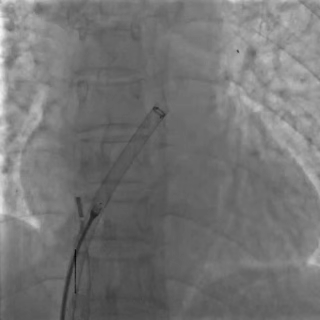

DSA下左盘展开,轻轻牵拉成型线辅助左盘成型,左盘1个Mark点靠近腰部2个Mark点

后撤钢缆和鞘管使左盘贴靠房间隔

右盘展开

后撤鞘管,展开右盘面,DSA下可见右盘1个Mark点靠近左盘和腰部3个Mark点

前顶钢缆和鞘管,牵拉成型线进行锁定,DSA下可见4个Mark点聚拢

牵拉试验

DSA下后退鞘管,轻轻牵拉钢缆,4个Mark点相对位置未发生变化,证明锁定成功

DSA下可见4个Mark点相对位置保持不变,整体随心博移动